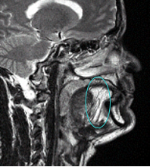

DTI fiber tracking shows IL fiber directions

Control

Fiber directions:

Green: anterior-posterior

Blue: superior-inferior

Red: lateral-media

Tongue is outlined in yellow

A radial forearm free flap replaced tissue removed in tongue cancer surgery

The flap appears white in the MRI because of its high fat content.